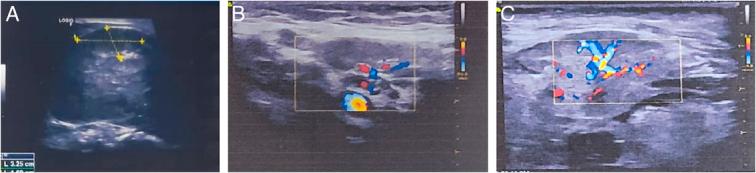

In a retrospective study between April 2021 and May 2023, 214 patients with CLA were assessed with preoperative US and FNAC. The morphological parameters, including tissue margins, vascularity, and fatty hilum echogenicity, were collected and analyzed retrospectively. The diagnostic efficacies of US, FNAC, and their combined use were compared to the postoperative histopathological findings.

在最终的组织病理学检查中,发现185例(86.4%)为良性,29例(13.6%)为恶性。脂肪门、回声和血管分布模式的US特征在表征CLA模式方面具有最高的诊断准确性,分别为88.3%、85.5%和85.0%。受试者工作特征(ROC)曲线显示,所有US参数联合使用时曲线下面积(AUC)值显著更高,为0.883(95%可信区间:0.832 - 0.923;<0.0001),其敏感性(93.10%)和特异性(68.65%)均优于单个参数。FNAC的总体敏感性、特异性和准确性分别为97.3%、82.8%和95.3%。此外,US参数和FNAC联合使用时AUC值显著更高,为0.924(95%可信区间:0.880 - 0.956;<0.0001),敏感性为86.21%,特异性为88.65%。